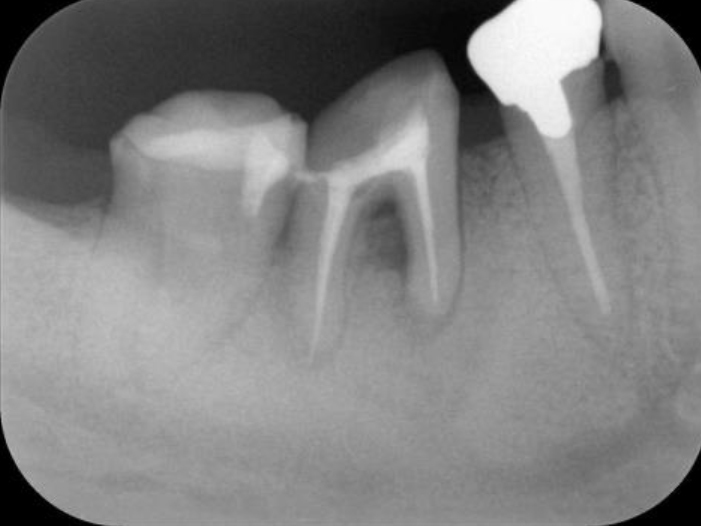

歯周基本治療・根管治療・歯周外科処置を行なった症例

初診時

浜松市中区の症例紹介 歯周外科

歯周基本治療・

根管治療後

歯周外科処置

歯周外科処置後

初診時(レントゲン)

歯周基本治療・根管治療後(レントゲン)

(レントゲン)